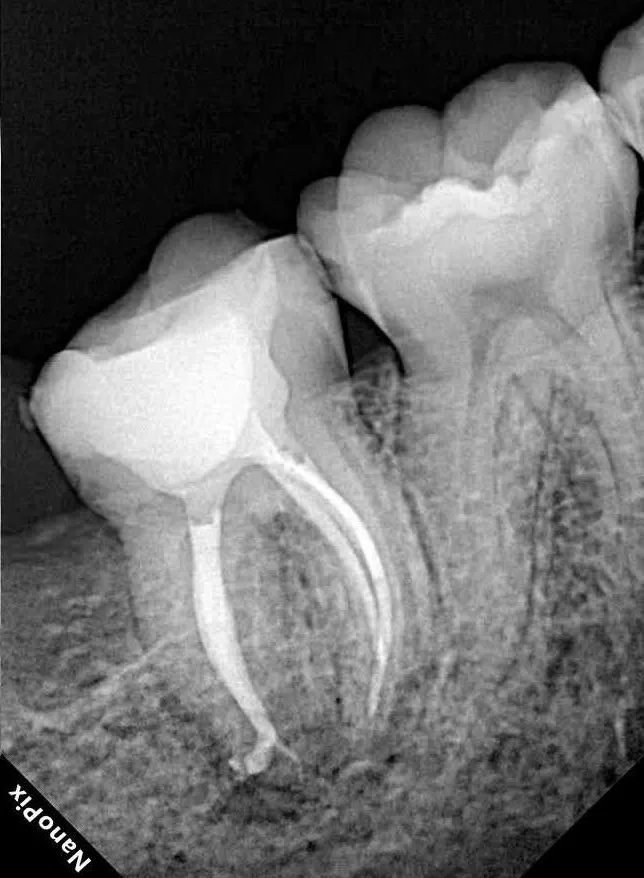

قبل

بعد